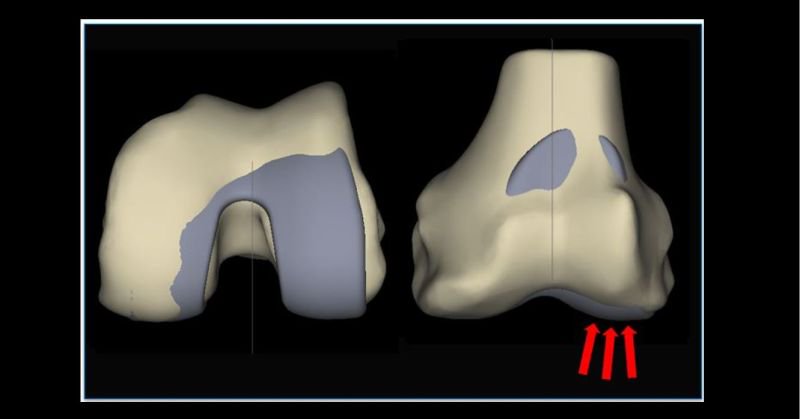

We welcome our first 'Bangor Zimmer Biomet hip and robotic knee fellow' Dr. Nishu Gupta to our unit. Week 2 - getting to know the ROSA. 37+ high BMI patient and 21.5-degree valgus deformity! Careful planning and perfect execution with the robot = great outcome! @kathryn_h_c